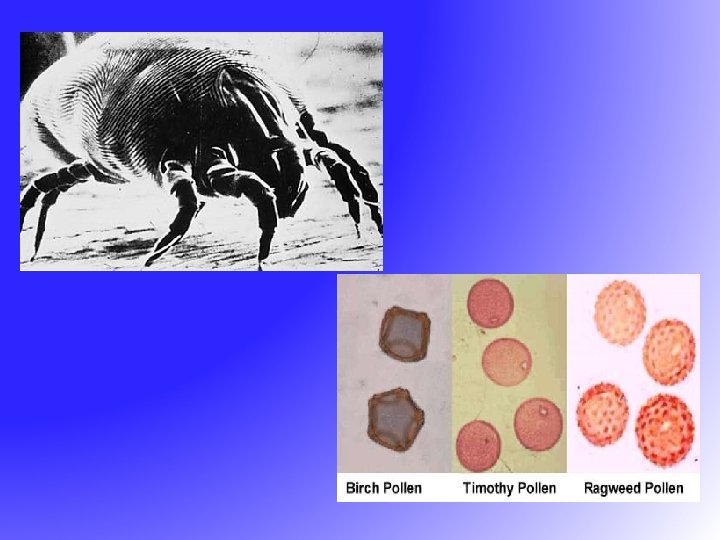

Allergic Rhinitis - Causes Seasonal (Intermittent) • Pollen from ü Grasses ü Weeds ü Trees • • • Perennial (Persistent) House dust mites Mold and fungus spores Cockroaches Animal dander Food Chemicals

Allergic Rhinitis - Causes Seasonal (Intermittent) • Pollen from ü Grasses ü Weeds ü Trees • • • Perennial (Persistent) House dust mites Mold and fungus spores Cockroaches Animal dander Food Chemicals

Allergic Rhinitis ü +ve family history ü Personal history of atopic disease e. g eczema, urticaria and asthma

Allergic Rhinitis ü +ve family history ü Personal history of atopic disease e. g eczema, urticaria and asthma